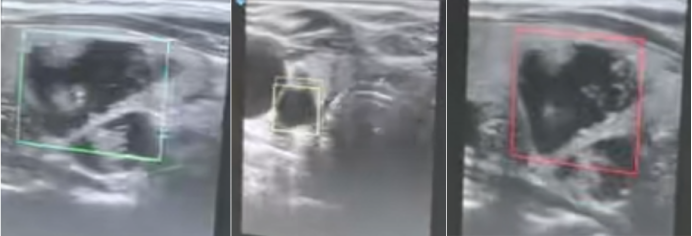

2.1  病情判定与组织分割

AI辅助判定病情场景中,结合图1可见:绿色方框标注位置,AI识别判定为存在异常表现;黄色方框标注区域,AI提示该部位需重点关注;红色方框标注处,AI建议在此位置优先开展核心诊断,为临床病情判定提供指向性参考 ,辅助医护人员更高效地识别关键病情信息。

1  AI辅助判断病情